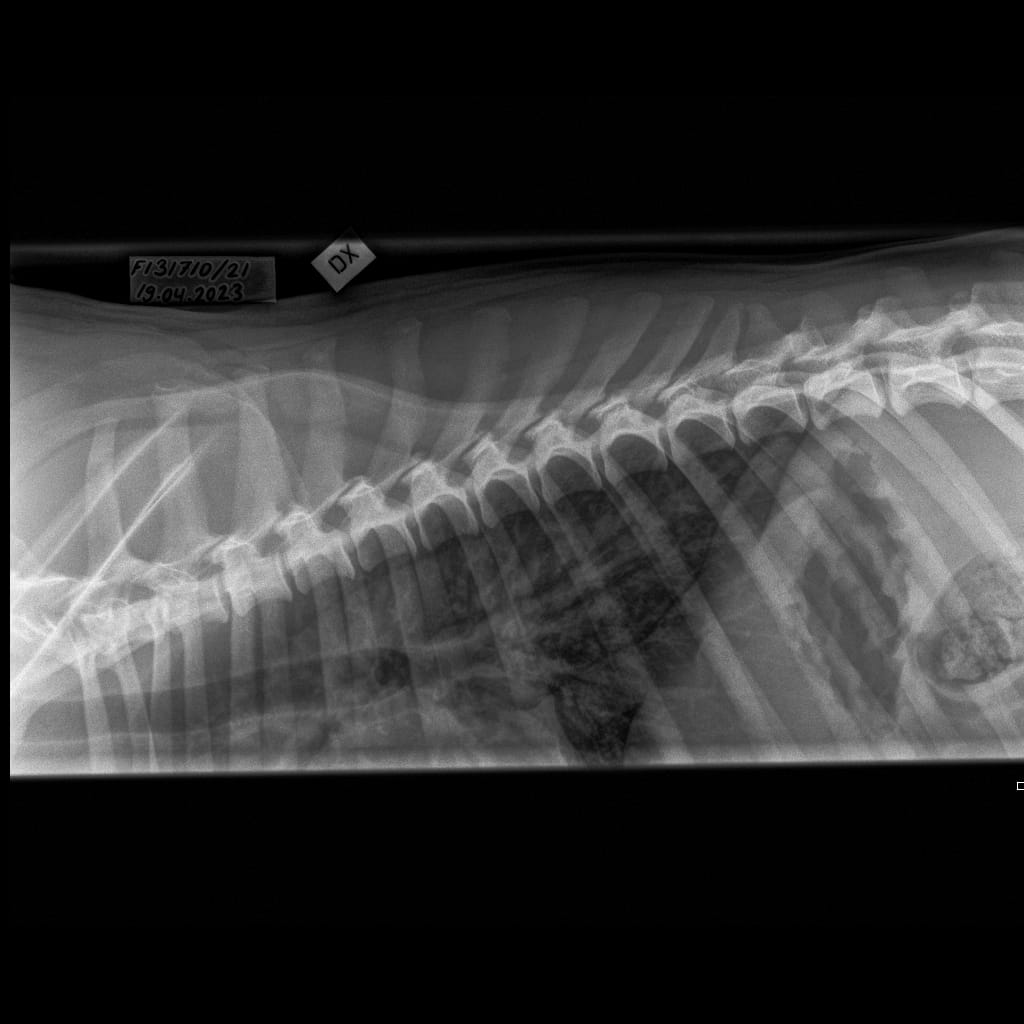

Selkäranka -Rintaranka LAT-6.11.2023-16_02_17-358